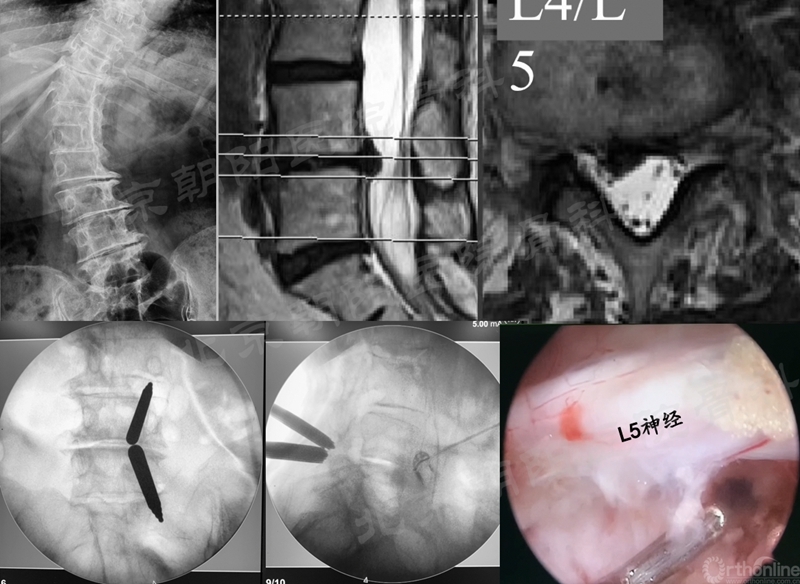

#10例UBE, L4/5 LSS。

术前MRI和术中定位